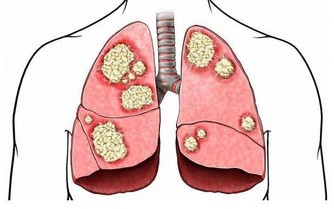

得了食管癌與賁門癌以後怎麼辦?這是個非常現實的問題。